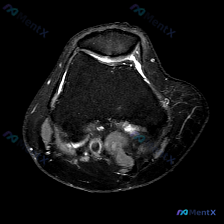

今天遇到一个挺典型的临床情况,整理出来和大家聊聊:核心问题是临床观察提示「软骨异常」,但我们拿到的单幅膝关节MRI冠状位T2加权像分析却全是阴性结果,一起来理理思路。 先给大家放完整影像信息: 1. 整体结构对位:股骨远端胫骨近端对位正常,无骨折错位 2. 骨髓信号:股骨髁、胫骨平台骨髓信号大致均匀...

看到这个病例挺有代表性,整理了完整资料和分析思路分享给大家。 病例基本资料 本次分析基于1张膝关节T2加权轴位MRI(髌股关节层面),临床提示为「软骨异常」,具体临床症状未提供。 影像学所见 1. 髌股关节结构:髌骨位于滑车槽中央,对位关系尚可,无明确脱位/半脱位;关节间隙无狭窄,仅可见少量生理性高...

刚梳理完一份膝关节MRI读片病例,核心问题是「这张图像中可视觉识别的潜在异常是什么?」,标准答案提示是软骨异常,不过整理完发现这个病例其实挺值得讨论,分享一下完整分析思路。 病例影像基础信息 这是一张膝关节MRI冠状位影像,我们先整理客观观察到的所有征象: 1. 骨骼结构:股骨远端、胫骨平台骨皮质连...